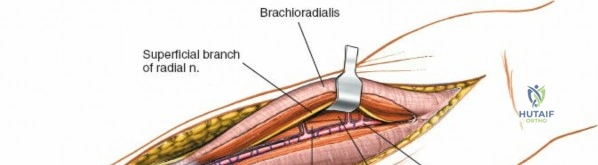

Incise the deep fascia of the forearm in line with the skin incision. The initial goal is to identify the medial border of the brachioradialis as it courses down the forearm. It is a common pitfall to search for this border too far laterally. At the level of the elbow, the brachioradialis is expansive and extends almost halfway across the anterior forearm. It is surprisingly easy to mistake the plane between the brachioradialis and the extensor carpi radialis longus for the correct intermuscular plane.

To confirm the correct plane, look for the superficial branch of the radial nerve. This sensory nerve runs on the undersurface of the brachioradialis muscle. Once the true medial edge of the brachioradialis is found, develop the plane between it and the pronator teres (proximally) or the flexor carpi radialis (distally). Retract the brachioradialis laterally, taking care to keep the superficial radial nerve attached to its undersurface to protect it from traction injury.